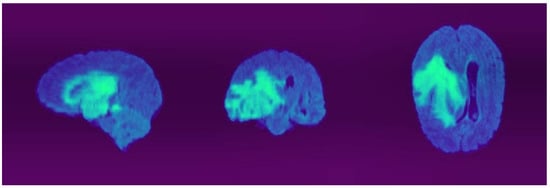

4.4. Quantitative and Qualitative Results